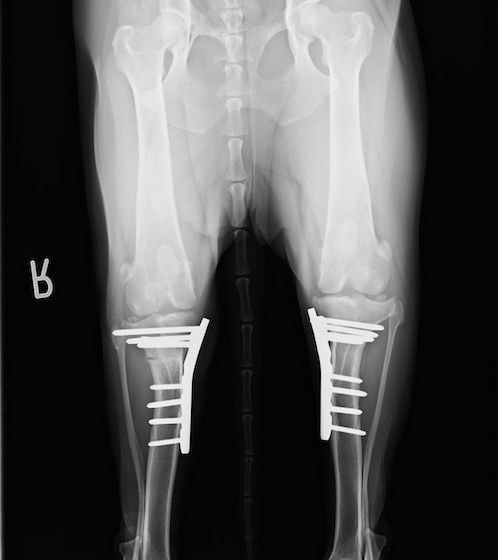

雑種 5歳

左後肢の挙上を主訴に来院されました。触診にて両関節の前方引き出し兆候、両膝蓋骨の内方脱臼を認めました。関節液検査より免疫介在性多発性関節炎は否定的でした。レントゲン検査にてfat pad signを伴う関節炎が認められたことから、前十字靭帯断裂と膝蓋骨内方脱臼(左GradeⅢ 右GradeⅢ〜IV)併発と診断し、手術を行いました。

手術は片足ずつ行い、両膝とも術中の関節鏡検査にて前十字靭帯の完全断裂と半月板損傷を確認しました。TPLO、半月板切除と滑車溝形成を始めとした膝蓋骨脱臼整復術を実施いたしました。膝蓋骨の安定化を測るために外側支帯を強固に縫合し、内側支帯は切除し縫合せずに開放状態にしています。

術後の歩行状態は良好です。

術前左後肢側面像

術前正面像

術後左後肢側面像

術後左後肢正面像

術前のTPAは左後肢33.1°右後肢26.8°でしたがTPLO実施により左後肢5.5°右後肢12°に矯正されました。